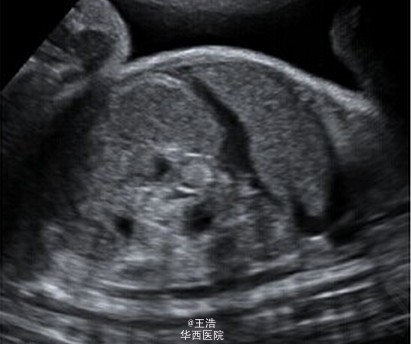

一名 35 岁初产妇,孕龄到达 30 周时出现了宫缩征象,但没有显示胎儿窘迫。超声显示胎儿发育,多普勒指数,羊水均正常。发现强回声的肠管轻度扩张,但不伴有形态学异常。病原体(TORCH)筛查阴性。第二天检查发现肠扩张伴有高回声点推断发生了进展并出现腹水,因此怀疑肠穿孔和胎粪性腹膜炎。 于是对产妇进行了紧急剖腹产。剖出一名男婴,重 2620g,在第 5 分钟及第 10 分钟 Apgar 得分都是 9 分。新生儿呼吸不稳定,腹部重度膨胀水肿呈铁青色,腹膜炎。对新生儿进行了紧急剖腹手术。术中发现证实了接生前的的诊断。切除了 50cm 坏死的回肠,且必要的实施了肠造口术。Takacs ZF, Meier CM, Solomayer EF, Gortner L, Meyberg-Solomayer G. 2014. Prenatal diagnosis and management of an intestinal volvulus with meconium ileus and peritonitis. Arch Gynecol Obstet. 290(2): 385-7.